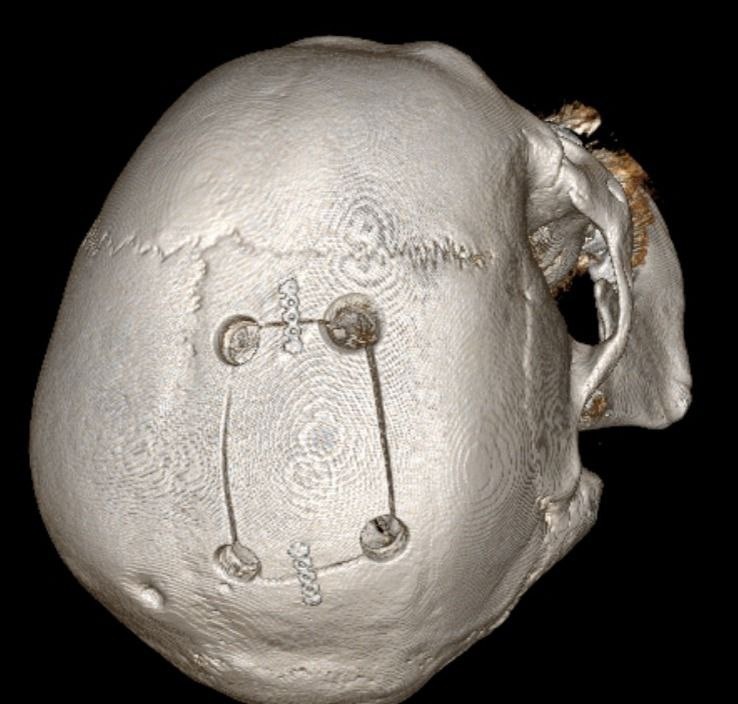

Когда 85-летний мужчина поступил в больницу у него уже отказала левая нога и левая половина тела. Изначально врачи подозревали инсульт. Но после проведеденного экстренного обследования, выяснилось, что его жизни угрожает опухоль размером 8x7 см.

Мужчине провели срочную операцию. Нейрохирурги Пятигорска выполнили трепанацию черепа и полностью удалили опухоль.